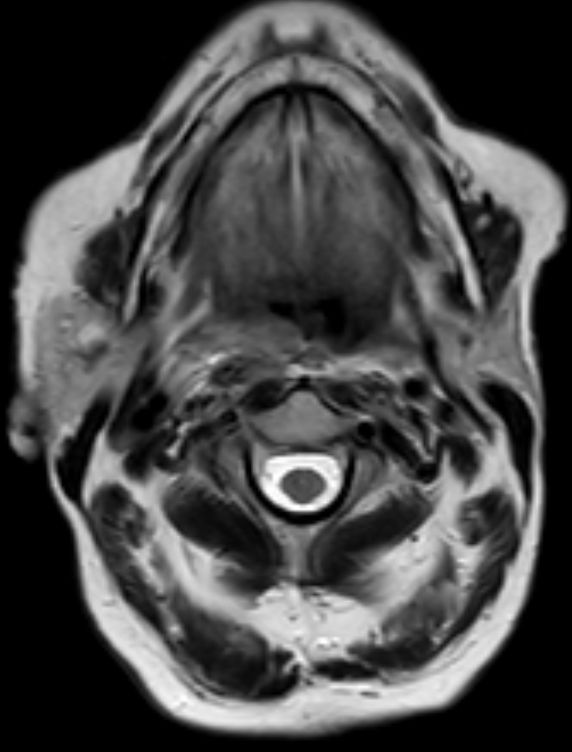

| Diagnostik | 88-jährige Frau mit einer progredientes

Dysphagie. Es besteht eine Raumforderung rechts retropharyngeal. Mukosa intakt.![]()  |